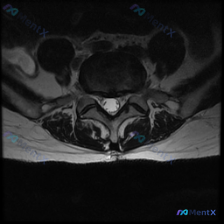

这是一份单张腰椎MRI T2轴位影像的分析病例,核心问题是:临床怀疑椎间盘病变,影像上能看到什么问题?整理了完整的读片和分析思路分享给大家。

本次提供的是腰椎MRI T2序列轴位单一层面图像,定位为腰椎椎间盘层面,我们按结构逐一读片:

- 骨性结构与韧带:椎体形态、骨皮质连续,无骨折或破坏;双侧关节突关节对称,间隙清晰,无明显增生骨赘;黄韧带厚度正常,无增厚钙化。

- 椎间盘评估:髓核T2信号正常,无显著减低,保持较好水合,没有明显变性脱水;椎间盘后缘轮廓平整,未见局限性突出或脱出;没有椎间盘组织突入椎管或侧隐窝,无占位压迫效应。

- 椎管与神经结构:硬膜囊形态规则,脑脊液信号饱满,无受压变窄;马尾神经分布均匀,无受压变形;双侧侧隐窝开阔无狭窄,椎间孔脂肪填充良好,神经根出口通畅。